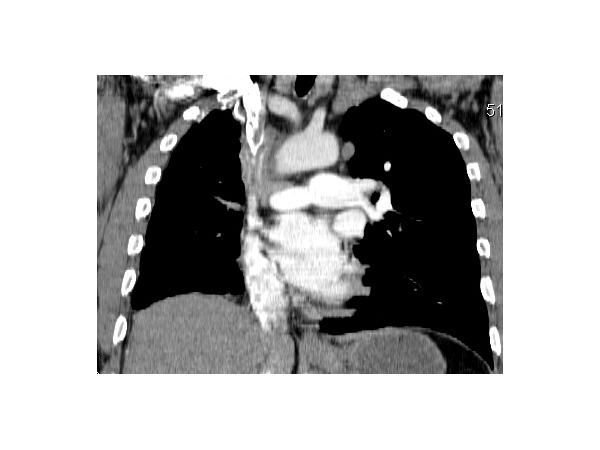

КТ грудной клетки показала:

- смещение средостение вправо;

- уменьшение объёма правого лёгкого;

- единичные плотные очаги;

- утолщение плевральных листков справа;

- сужение и изменение формы бронхов правого лёгкого, утолщение их стенок;

- небольшие отложения кальция (кальцинаты) в просвете правой лёгочной артерии;

- образование неправильной формы размером 53×36 мм без чётких контуров в проекции артерии;

- распространение образования на правый бронх, корень правого лёгкого и до 55 мм вверх по ходу верхней полой вены;

- резкое нитевидное сужение просвета верхней полой вены, видны кальцинаты;

- множество расширенных извитых вен в средостении и области грудной стенки.